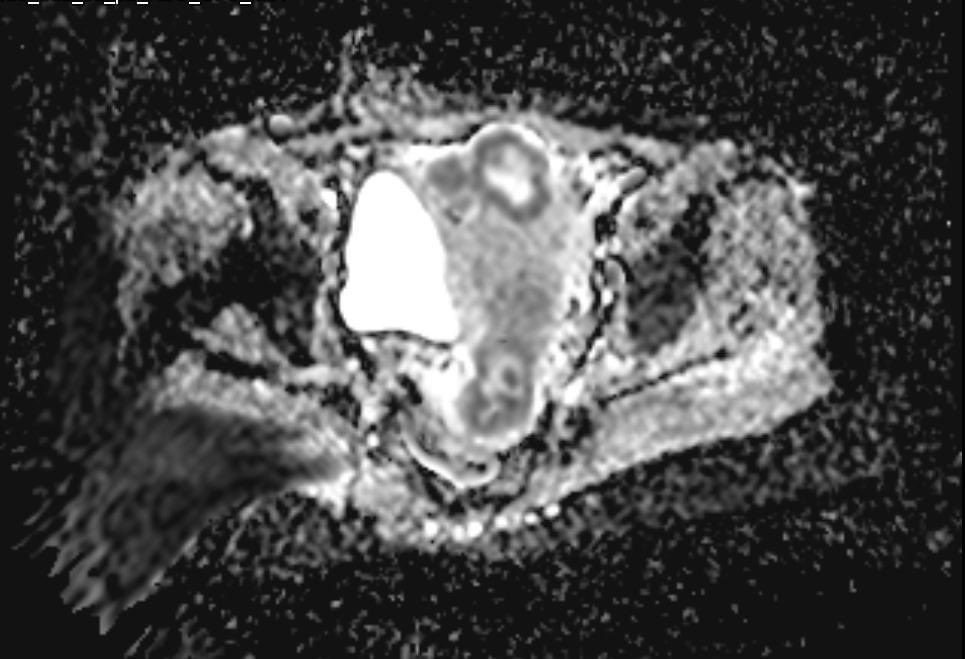

58-year-old female with active vaginal bleeding #Findings: •There is thickening of the endometrium measuring 14mm in thickness with internal intermediate signal intensity seen. •The lesion is seen extending into the myometrium with invasion of the serosa layers. •The lesion

hemo_shk's tweet image. 58-year-old female with active vaginal bleeding

#Findings:

•There is thickening of the endometrium measuring 14mm in thickness with internal intermediate signal intensity seen.

•The lesion is seen extending into the myometrium with invasion of the serosa layers.

•The lesion

- 58-year-old female with vaginal bleeding for the past 2 months - findings and diagnosis ? #MEDHM @IhabFathiSulima #MedEd #MedX

hemo_shk's tweet image. - 58-year-old female with vaginal bleeding for the past 2 months

- findings and diagnosis ?